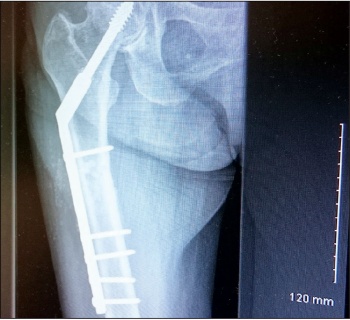

An 83-year-old woman presented to hospital with low energy trauma resulting in non-weight bearing and pain in her right thigh. She had chronic obstructive pulmonary disease (COPD), diabetes mellitus type 2, gastroesophageal reflux disease (GERD) and osteoporosis. She had a right neck of femur intertrochanteric fracture in 2010 for which she had a two-hole dynamic hip screw (DHS) plate.

She was started on alendronate therapy in 2011 for osteoporosis. She had left distal radius fracture in 2013 for which she had manipulation under anaesthesia and k-wiring. She had a low energy trauma in January 2015 and was brought in with right thigh pain and non-weight bearing.

She had an x-ray right femur and pelvis showing an atypical right femur sub-trochanteric fracture. She was taken to the theatre the next day and her two-hole plate was removed without taking the lag screw and was replaced with an eight-hole DHS plate. She was started on physiotherapy and within a few weeks she was walking with a walking frame. She was followed up with regular x-ray. Her alendronate was stopped and she started on teriparatide injections. Teriparatide is a man-made form of the hormone parathyroid which exists naturally in the body.

Figure 1. DHS two-hold plate for neck of femur fracture(click to enlarge)